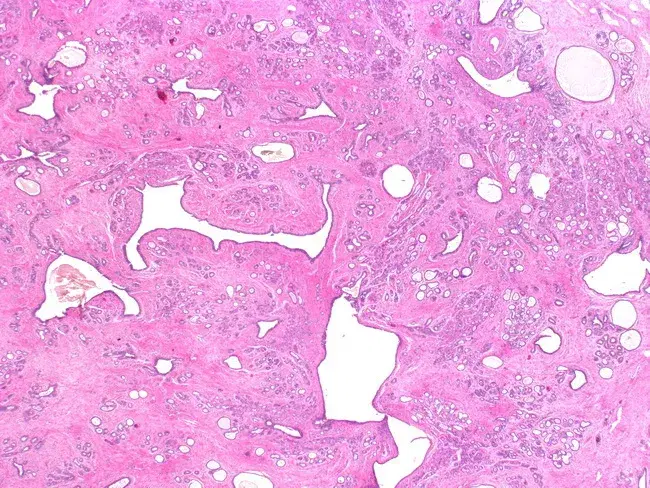

Anasayfa » Sözlük » Fibrokistik Meme Hastalığı